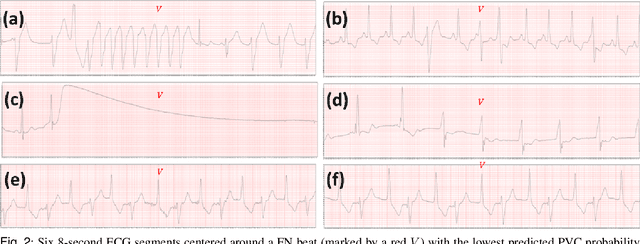

Abstract:Introduction: Premature Ventricular Contractions (PVCs) are common cardiac arrhythmias originating from the ventricles. Accurate detection remains challenging due to variability in electrocardiogram (ECG) waveforms caused by differences in lead placement, recording conditions, and population demographics. Methods: We developed uPVC-Net, a universal deep learning model to detect PVCs from any single-lead ECG recordings. The model is developed on four independent ECG datasets comprising a total of 8.3 million beats collected from Holter monitors and a modern wearable ECG patch. uPVC-Net employs a custom architecture and a multi-source, multi-lead training strategy. For each experiment, one dataset is held out to evaluate out-of-distribution (OOD) generalization. Results: uPVC-Net achieved an AUC between 97.8% and 99.1% on the held-out datasets. Notably, performance on wearable single-lead ECG data reached an AUC of 99.1%. Conclusion: uPVC-Net exhibits strong generalization across diverse lead configurations and populations, highlighting its potential for robust, real-world clinical deployment.